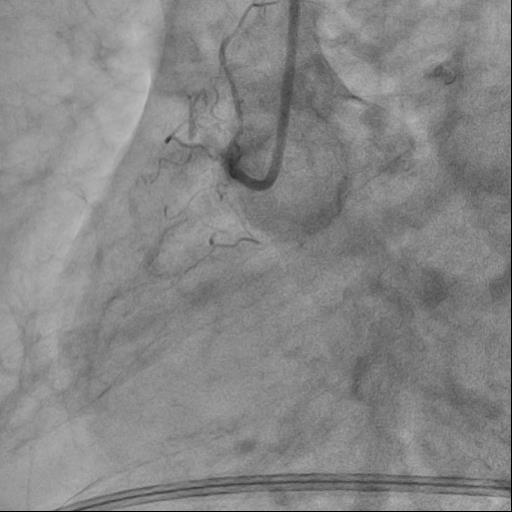

The guide catheter was selectively placed at the RCA orifice, several attempts at antegrade recanalization were performed, after 10 minutes a decision was made to perform retrograde recanalization of the RCA, Sion Blue with the support of a Corsair 150cm microcatheter was successfully introduced through the septal branch into the middle segment of the RCA, escalation to Gaya 2 was performed and recanalization of the RCA was performed. Tip-In was performed in the antegrade guide catheter, the retrograde coronary guide was fixed with a balloon catheter. The retrograde microcatheter was advanced into the proximal segment, however, when performing Corsair, its defragmentation occurred, and the tip of the microcatheter itself was torn off. A decision was made to perform repeated recanalization of the RCA in a new lumen. Recanalization was successfully performed, then Tip-In was performed into the antegrade microcatheter and its successful passage beyond the occluded area. Balloon angioplasty and stenting of the RCA under OCT control with vFR.